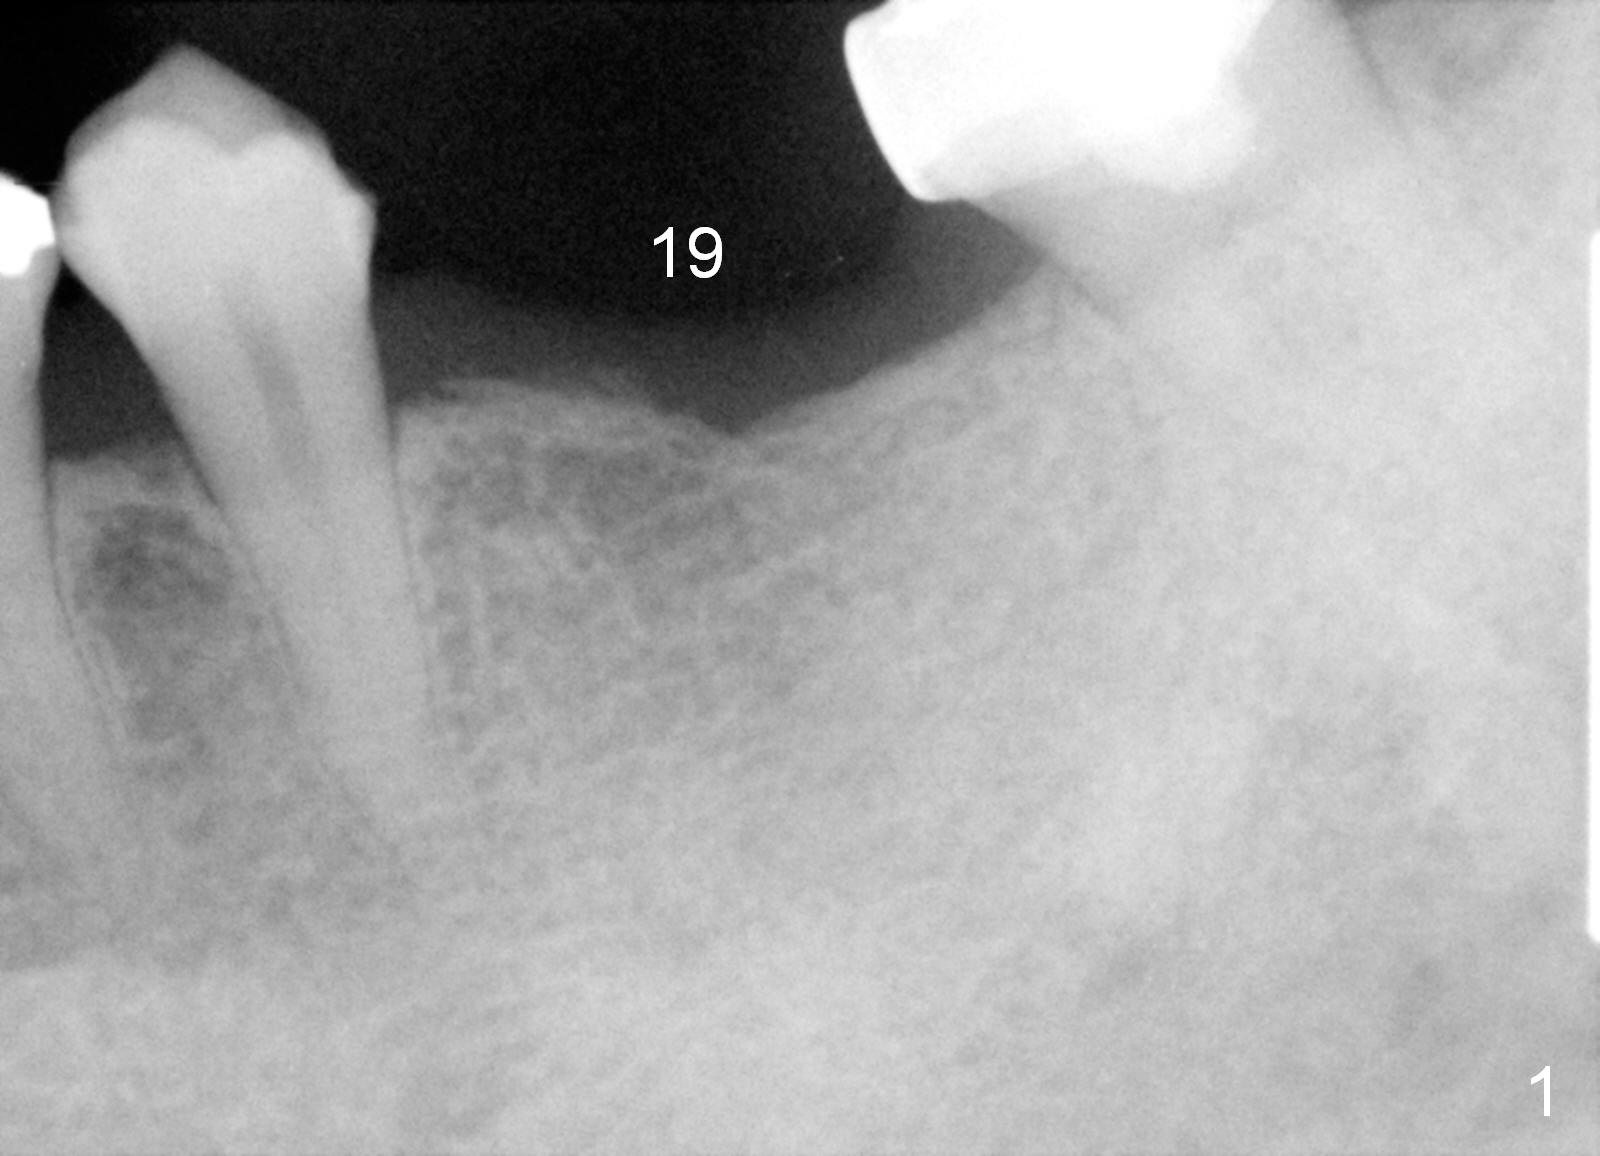

A 45-year-old man has lost the tooth #19 for about a decade (Fig.1). In spite of this, the ridge is not particularly narrow. The bone height is good for 14 mm bone-level implant (Fig.2). After incision, initial osteotomy depth is 12 mm. Insert a short parallel pin for occlusal check and a depth-marked parallel pin for X-ray. When the depth is adjusted, use drills with stoppers to finish osteotomy. If bone density is low, the drill is one size smaller than the expected implant.